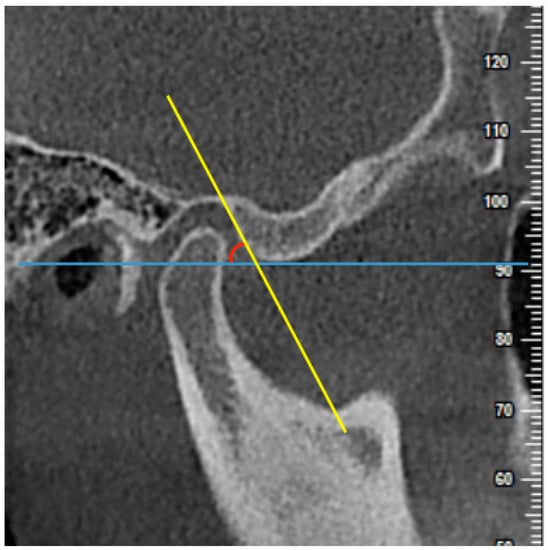

2.4. Measurements